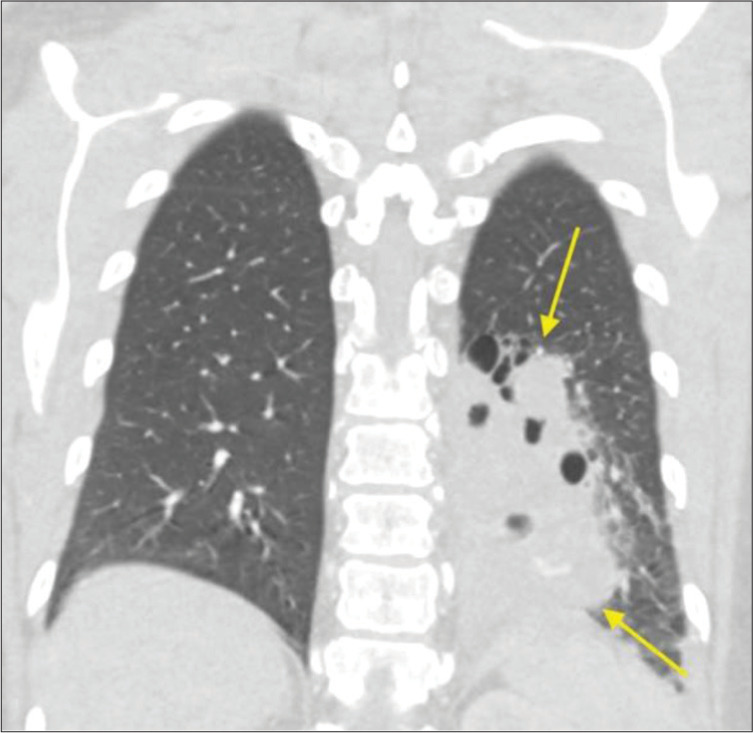

Pulmonary sequestration is a malformation of lung tissue such that a zone of pulmonary parenchyma exists in isolation from the bronchopulmonary tree. This condition is typically treated with surgical resection, but an increasing number of sequestrations are being treated with arterial embolization. We report interventions that were performed at two institutions on patients 53-70 years old. One patient presented with chronic cough and the two other patients presented with hemoptysis. Two of the cases were managed solely by endovascular embolization of the arteries supplying the pulmonary sequestration. In one patient, embolization was performed to debulk the sequestration, followed by surgical resection. These cases suggest transcatheter embolization may be an effective treatment in adult patients with symptomatic pulmonary sequestrations.